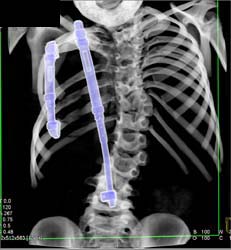

Lung Cancer Metastatic to Subcutaneous Tissue